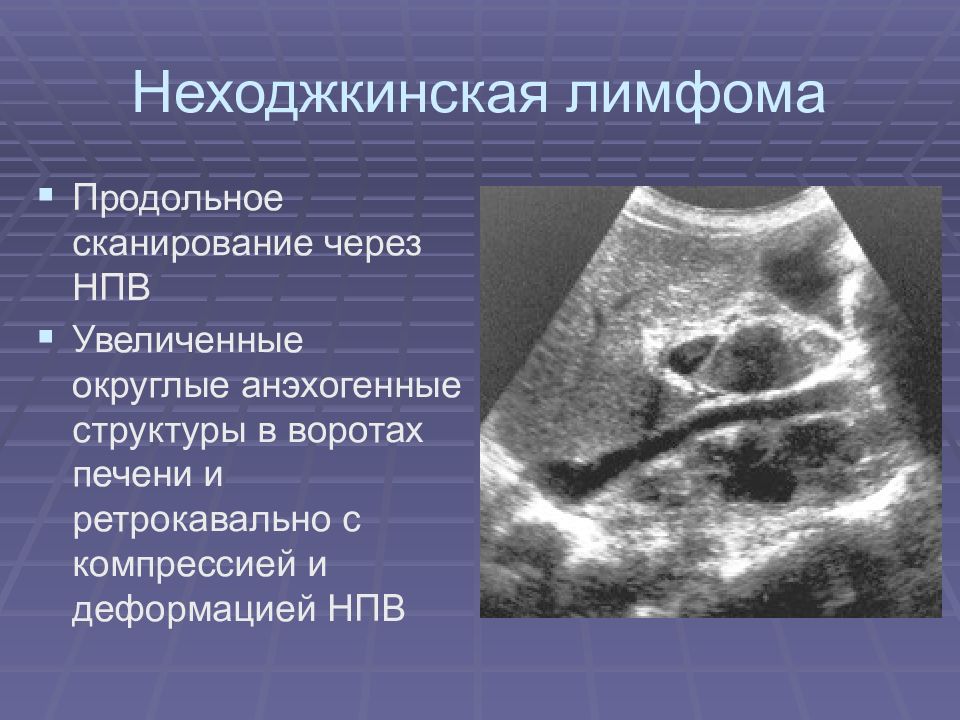

Как выглядит доля Риделя на УЗИ печени